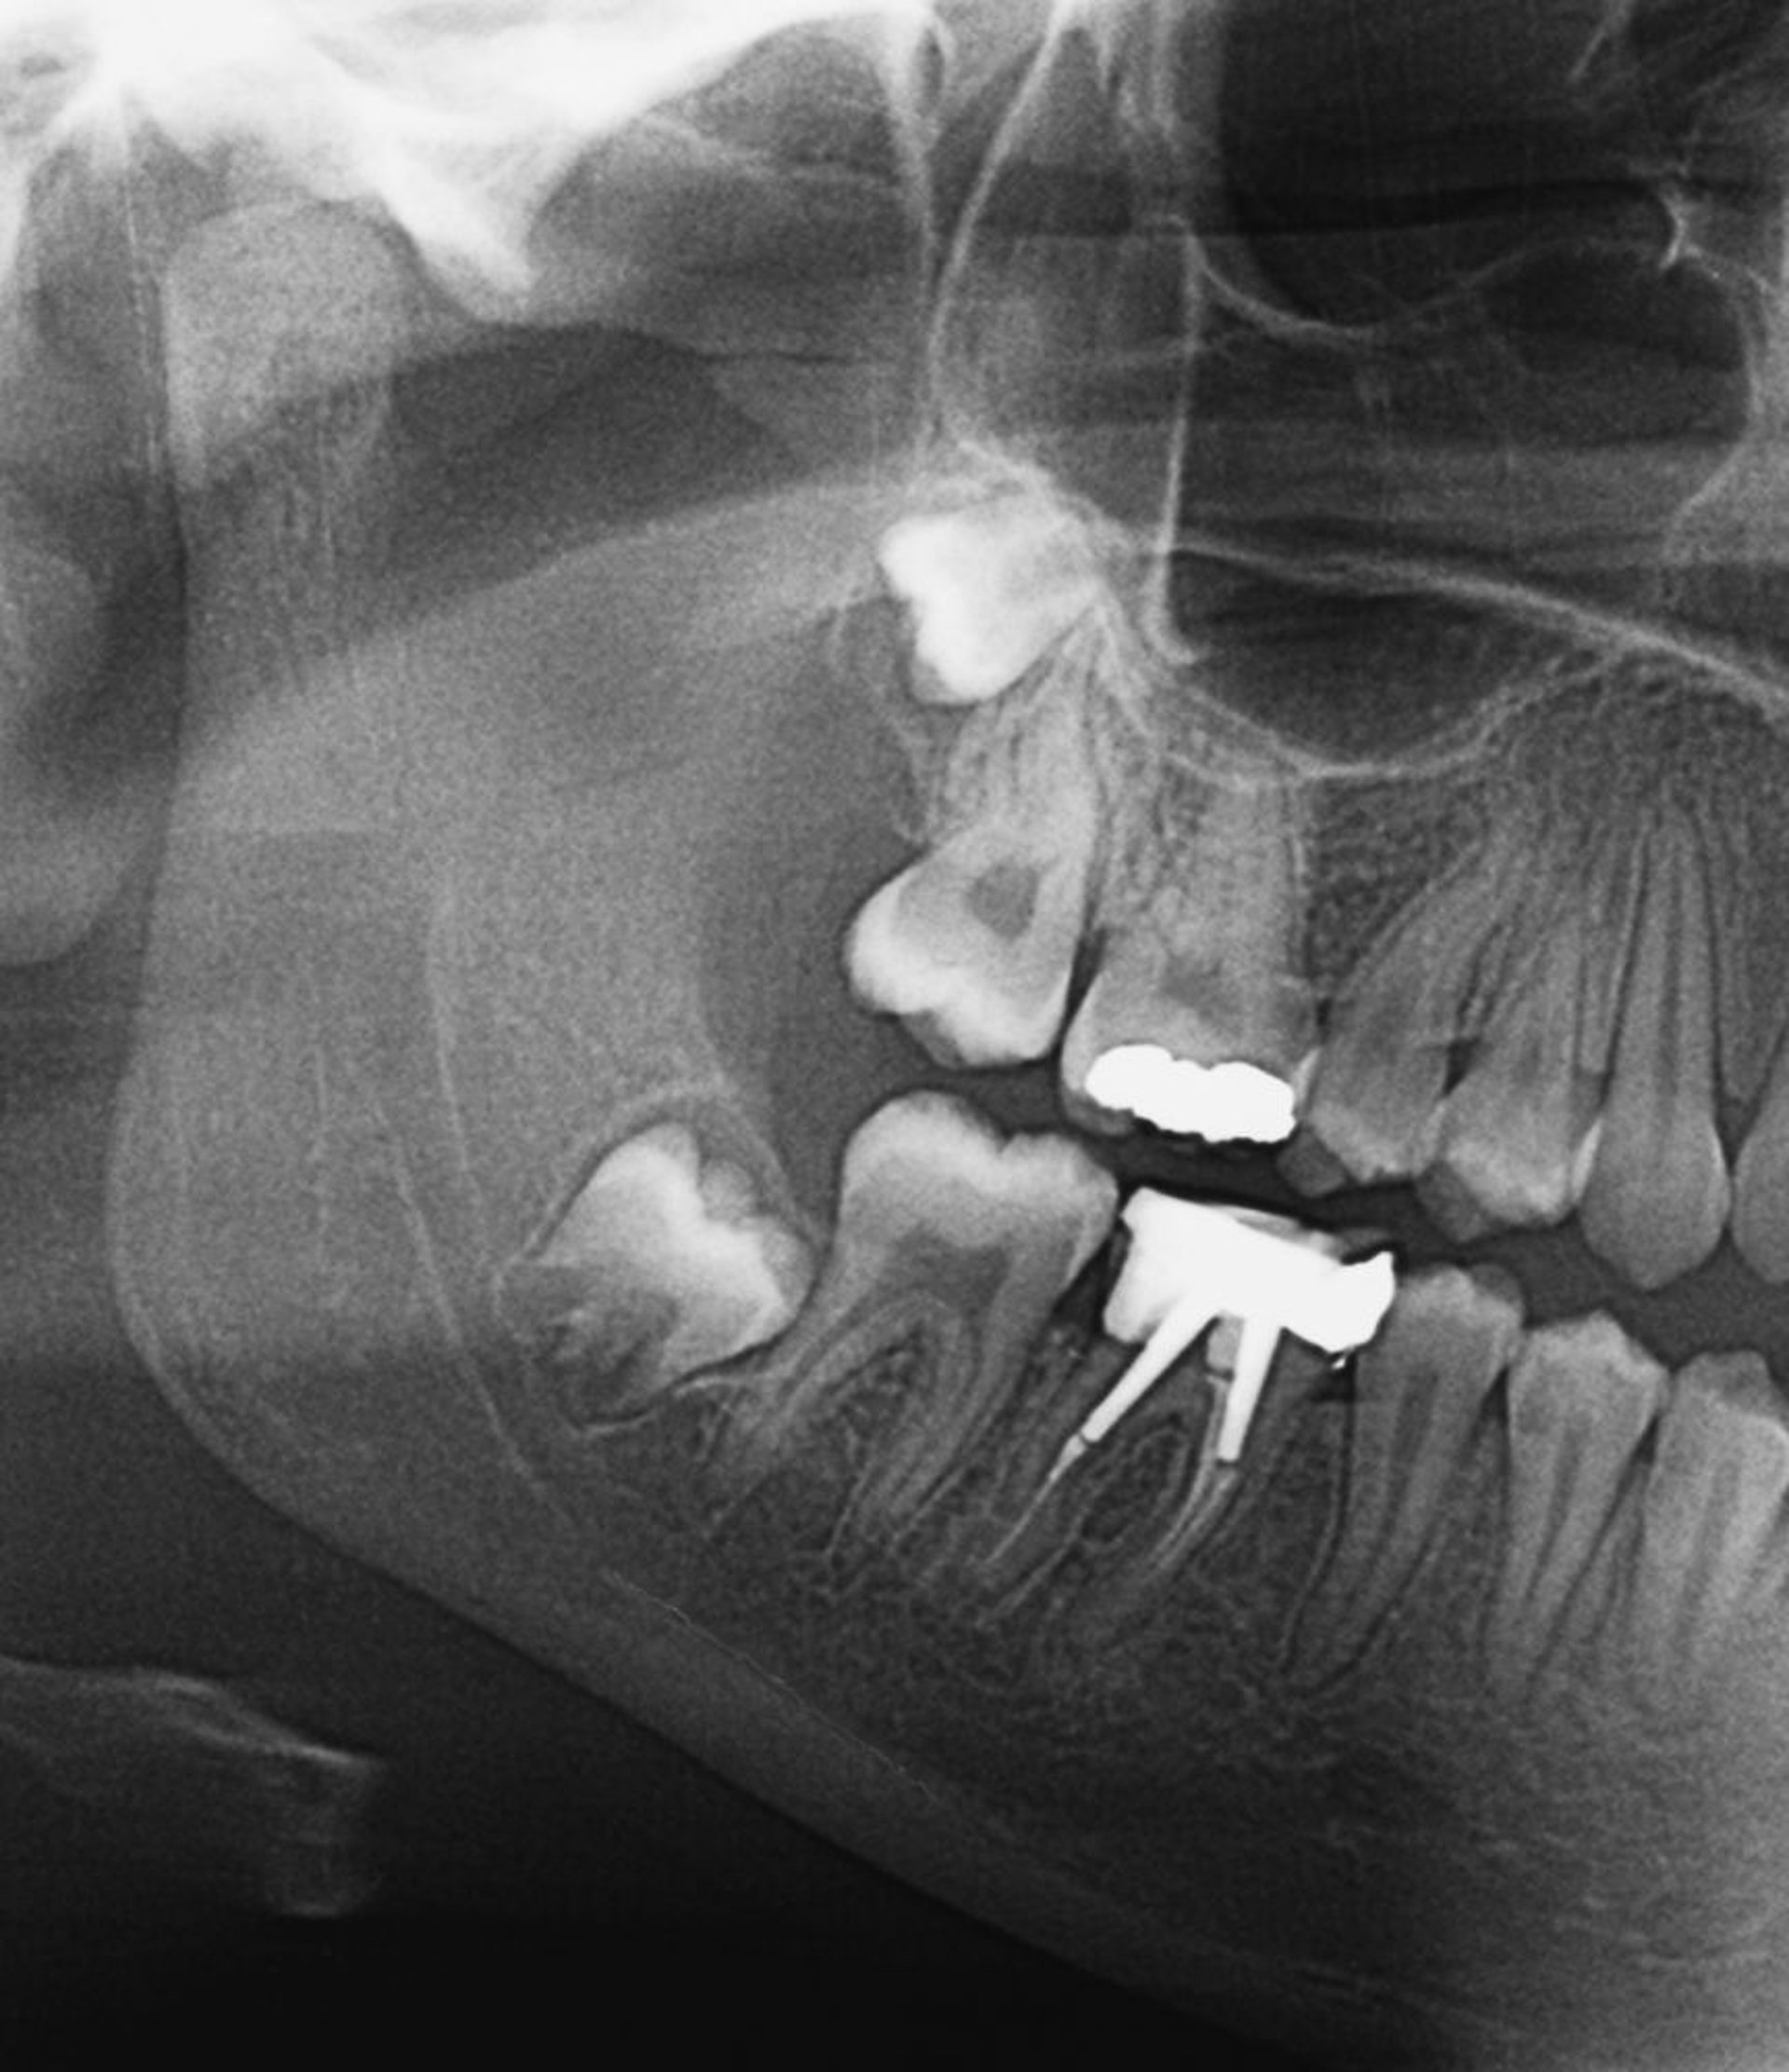

This x-ray shows impacted wisdom teeth. As wisdom teeth erupt, or if they are partially impacted, pericoronitis can develop.